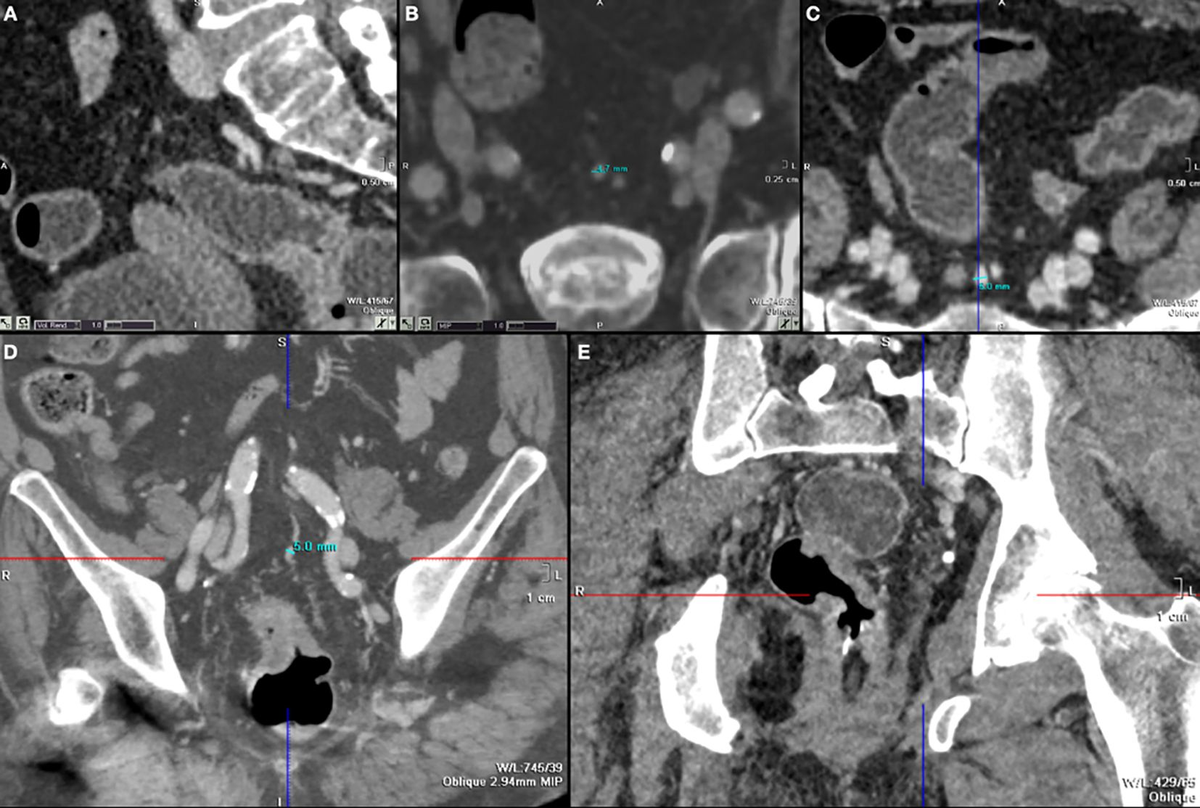

Qualitative and semi-quantitative ultrasound assessment in delta and Omicron Covid-19 patients: data from high volume reference center | Infectious Agents and Cancer